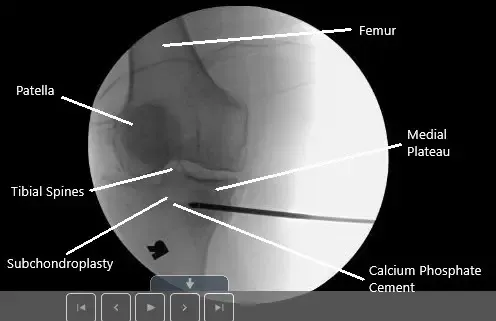

Imagen fluoroscópica intraoperatoria de subcondroplastia.

Ahora, la atención se centró en la fijación de la fractura por estrés de la meseta tibial medial. La cánula se introdujo desde la subcondroplastia situada medialmente bajo control del brazo C, aproximadamente un centímetro por debajo de la superficie articular. Fue insertado en dirección anterolateral.

La cánula fue revisada en vista avanzada y lateral y se encontró en una posición adecuada. El cemento de fosfato de calcio subcondroplastia se insertó usando jeringuillas de 1 cc. Se utilizaron cinco jeringuillas.

Se podía ver el cemento llenando la región de la meseta tibial medial, superiormente, por encima de la cánula. Se dieron diez minutos para que el cemento se endureciera. La cánula fue retirada. La última foto fue tomada y guardada.